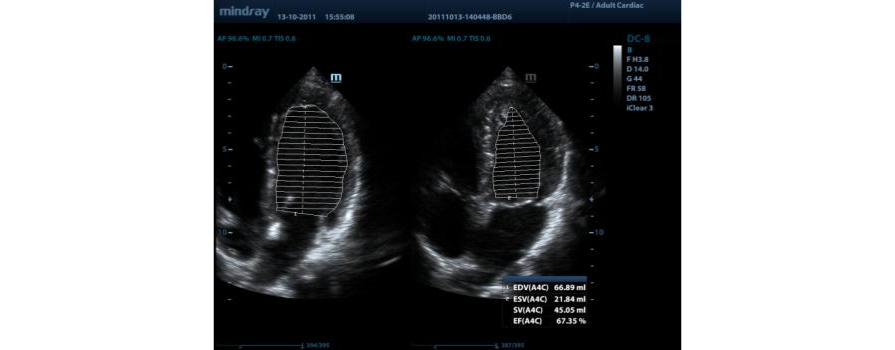

AutoEF

Een intelligente manier om 2D-echoclips zo te analyseren dat diastole/systoleframes automatisch worden herkend en EDV/ESV/EF-resultaten, enz. worden uitgevoerd via de Simpson-methode

Auto LV

Eenvoudige meetprocedure voor linkerventrikel, verbeterd door automatische traceerfunctionaliteit en eenvoudige handmatige correctie